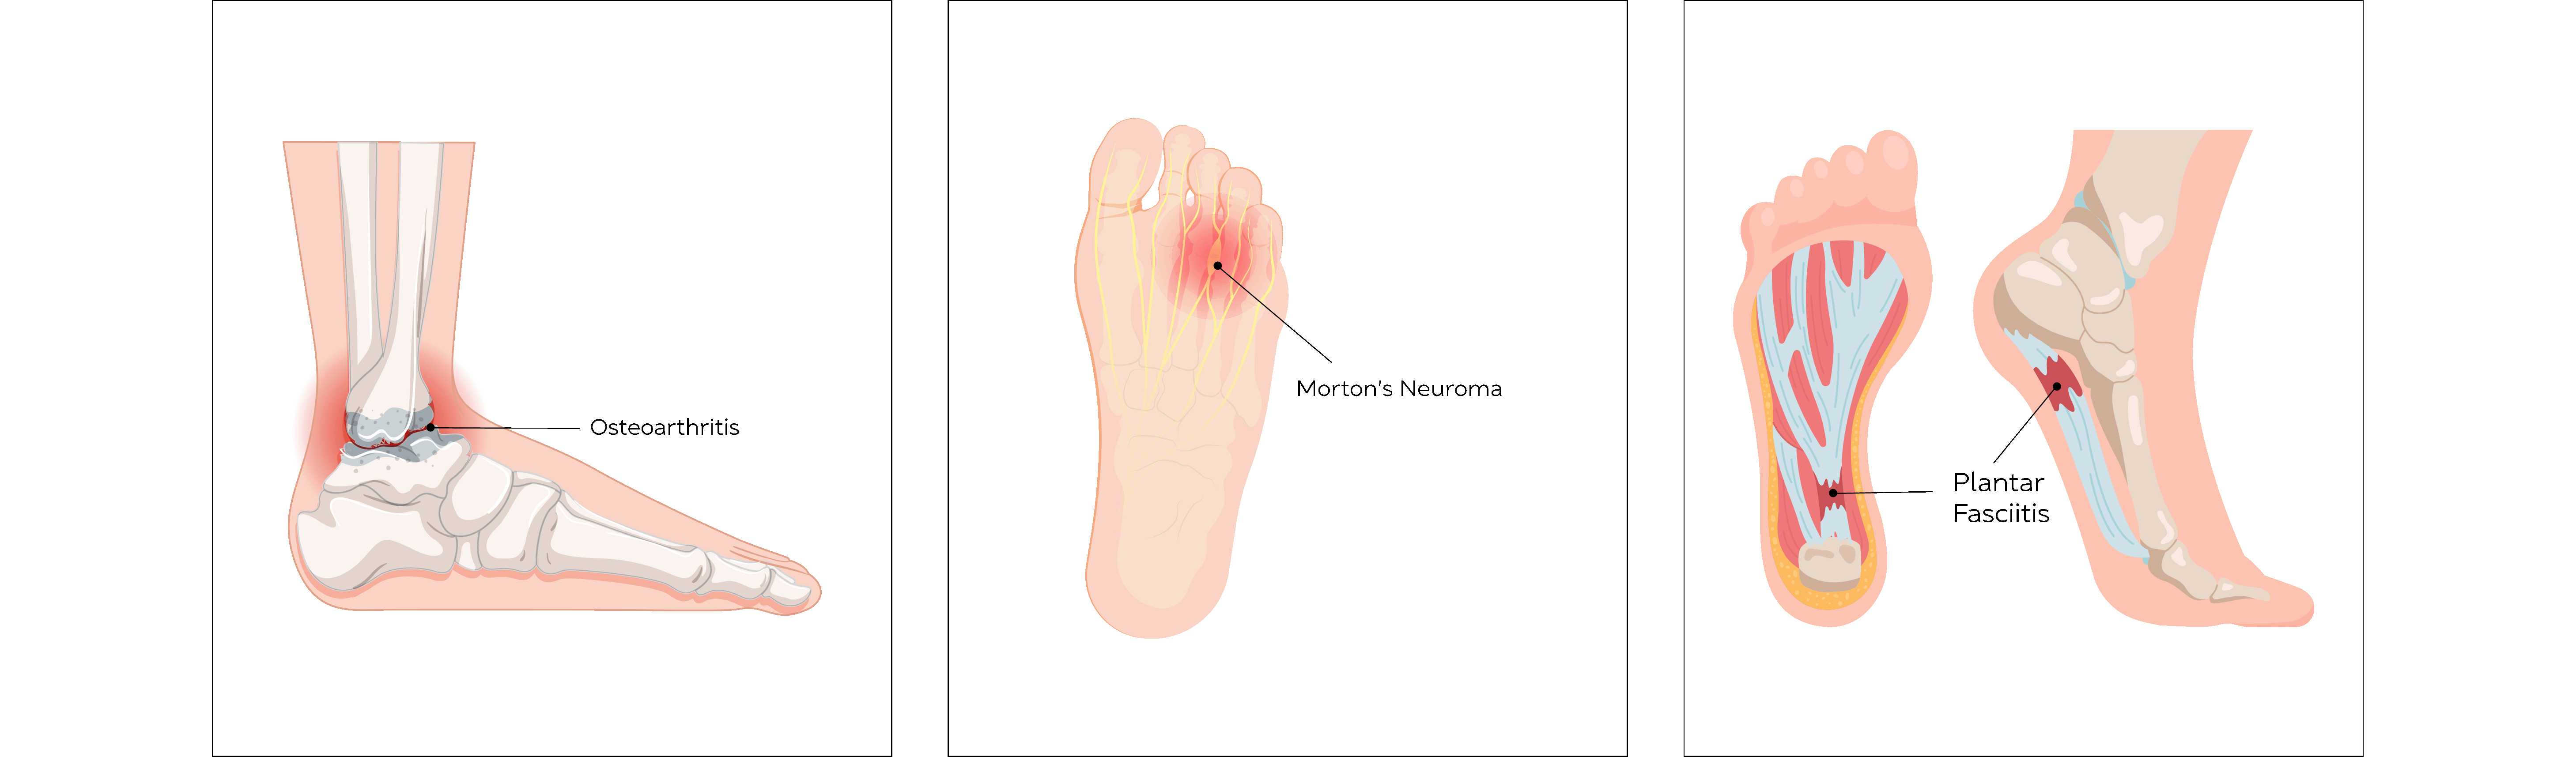

Plantar Fasciitis

Inflammation of a thick band of tissue that runs from the heel to toes at the attachment to the heel.

Affects 3-7% of the population.

The main symptom of plantar fasciitis is morning pain or pain at the beginning of activity after rest, which may worsen by the end of the day.

Ultrasound can be used both as a diagnostic tool and delivering treatment if other modalities of treatment fail to relieve symptoms. Guided injection using steroids relieve inflammation and aid in rehabilitation.

Morton’s Neuroma

Morton’s Neuroma is when a small digital nerve normally found between the bones of the forefoot gets inflamed and produces forefoot pain. Mostly seen between the 3rd and 4th toes.

This condition is seen predominantly in the female population and can affect up to 20% of the population in general.

Morton’s neuroma can present as sharp shooting pain in the forefoot with activities including weight bearing. Some patients report symptoms of walking on “pebbles”.

Ultrasound can be used to not only diagnose the condition, but also target steroid injections into the lesion and help relieve pain.

Arthritis of Ankle, Mid Foot & Big Toe

Osteoarthritis is a painful degenerative condition affecting any joint with articular cartilage due to gradual wear and tear of the articular cartilage, which protects the bone ends.

It is not as common as hip or knee osteoarthritis but is increasing in incidence.

Pain, swelling and restriction of joint movements and later physical deformity of the foot and toes can occur.

Osteoarthritis cannot be cured by medication, but injections administered into the joint using steroids or Hyaluronic acid do give short and long term relief of symptoms.